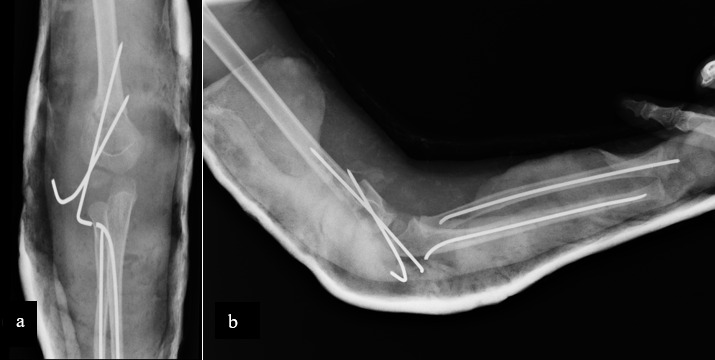

浮肘是指同侧肱骨和前臂同时骨折。这是一种不常见的损伤,极有可能导致前臂室压力升高,并可能造成破坏性的神经系统后遗症。已有多种治疗方法的报道。虽然在英文文献中已考虑过保守治疗,但在可能的情况下,经皮或微创固定是一个目标,软组织和生长板的保护对骨折愈合、活动度和骨生长至关重要。

Floating elbow is defined as concomitant fracture of ipsilateral humerus and forearm. It is an uncommon injury with high potential to develop elevated forearm compartment pressures with potentially devastating neurological sequel. Several treatments have been reported. Although conservative treatment has been considered in the English literature, percutaneous or minimally invasive fixations is a goal when it is possible, soft tissue and growth plate preservation is crucial for fracture healing, mobility and bone growth.